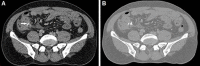

Foreign body (FB) ingestion is a common condition encountered in clinical practice, especially among the pediatric age group; however, this occurrence is rare among adults. Some FBs can induce the perforation of the gastrointestinal tract, including fish bones, chicken bones and toothpicks. The ingestion of FBs is rarely associated with bowel perforation, and most FBs are passed spontaneously. The ingestion of sharp and pointed objects typically produces adverse events related to the upper gastrointestinal system, and FBs are rarely retained in the colon. Bowel perforation caused by the ingestion of FBs should be diagnosed and treated in a timely manner. Here, we present the unusual case of a 51-year-old male who presented to the emergency room with complaints of acute abdominal pain secondary to fish bone ingestion, which triggered cecum perforation.